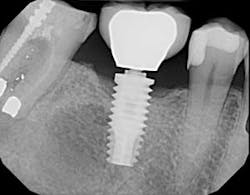

The screw channel of the abutment was accessed by carefully drilling a hole in the center of the occlusal surface using a cross-cut 557 bur (Brasseler) and progressively widening it until the screw channel was accessed (figure 10). Once the screw channel was accessed, the cavit and cotton blocking the screw were removed and the screw was visualized. A driver was placed into the channel to engage the screw and the cement-retained crown was seated on the implant and “screwed” back in place. Complete seating of the restoration was verified radiographically (figure 11). The screw was torqued to 25 Ncm and the access channel was filled with Teflon tape and closed with composite (figure 12). The patient was able to leave with the crown securely in place.

Figure 11:Complete seating of the restoration confirmed radiographically.